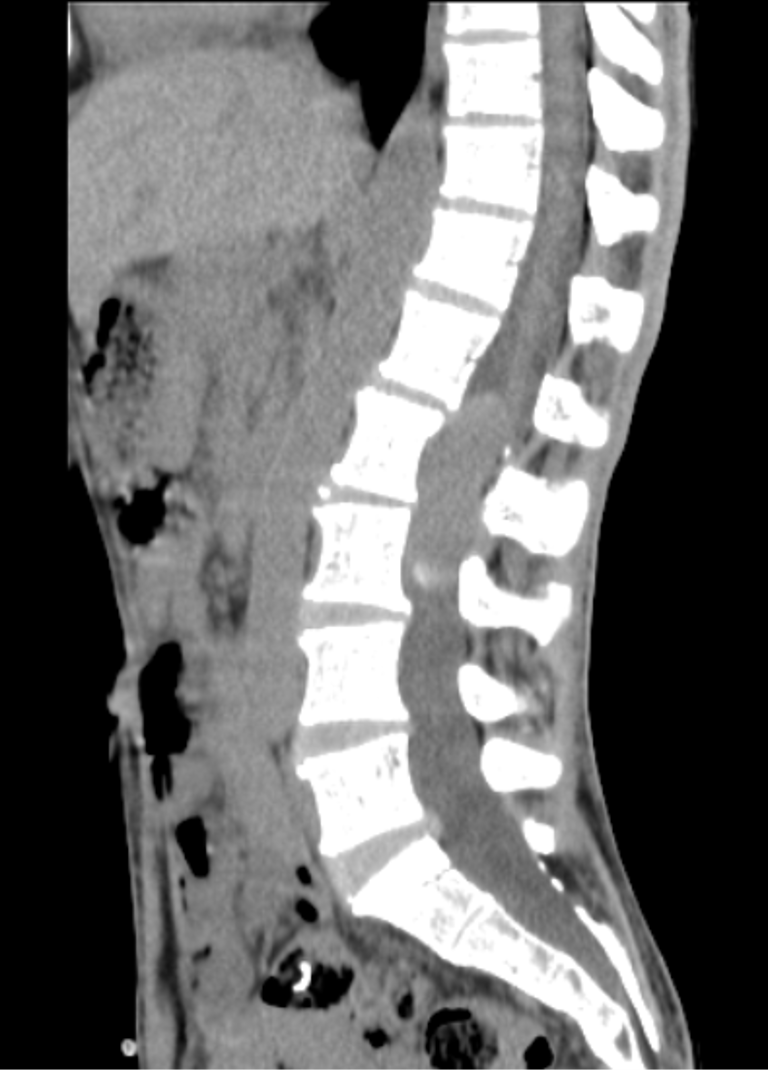

CT

In the present case, the lesion demonstrates T1 hyperintensity and T2 hypointensity, an atypical appearance attributed to dense keratinaceous debris, cholesterol crystals, high protein concentration, and chronic desiccation, resulting in shortening of T1 and T2 relaxation times. Such lesions are described as atypical or “white” epidermoid cysts.

Associated scalloping of the lumbar vertebral bodies reflects chronic, slow-growing mass effect, further supporting the benign and indolent nature of the lesion.